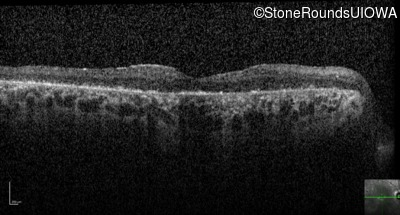

Optical Coherence Tomography - Right - 5/400

Exemplar / OCT Stack

OCT Stack